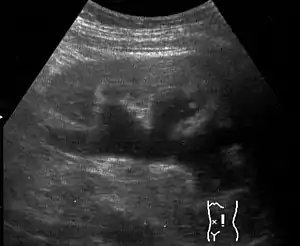

| Renal ultrasonography of hydronephrosis caused by a left ureteral stone. | |

Imaging studies, such as an intravenous urogram (IVU), renal ultrasonography, CT, or MRI, are also important investigations in determining the presence and/ or cause of hydronephrosis. Whilst ultrasound allows for visualisation of the ureters and kidneys (and determine the presence of hydronephrosis and / or hydroureter), an IVU is useful for assessing the anatomical location of the obstruction. Antegrade or retrograde pyelography will show similar findings to an IVU but offer a therapeutic option as well. Real-time ultrasounds and Doppler ultrasound tests in association with vascular resistance testing helps determine how a given obstruction is effecting urinary functionality in hydronephrotic patients.[10]

Massive hydronephrosis as marked by the arrow.- Renal ultrasonography of hydronephrosis[14]